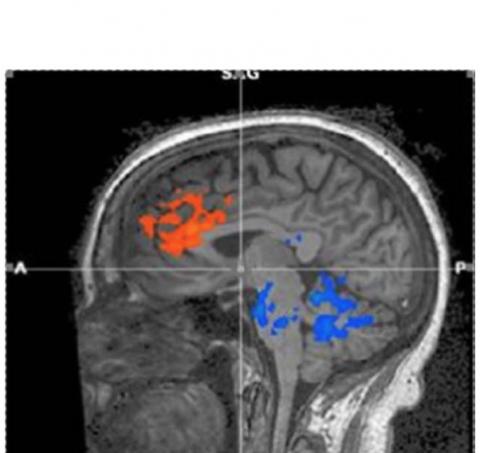

L’étude montre en effet que cet état est plus qu'un concept ou une allégation mais se traduit par des modèles de flux sanguin qui apportent une image physiologique de la réalité de la vigilance reposante dans l'esprit et le corps :

- L’augmentation (en orange) du flux sanguin est en effet constatée vers les zones du cortex préfrontal associées à l'attention et aux fonctions exécutives telles que la prise de décision, le raisonnement, la mémoire de travail, l’inhibition et l’anticipation de récompense.

- La diminution (en bleu) du flux sanguin vers le pont impliqué dans la régulation de l'état général d'excitation, des rythmes respiratoires et cardiaques soutient l’idée que la méditation transcendantale apporte « un repos » au corps et « un silence » à l’esprit.